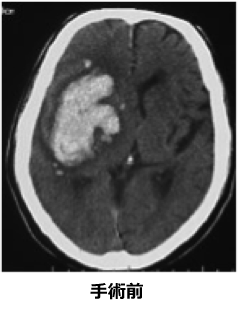

ただ、病院を受診した時にはすでに血の塊が大きく命に関わりそうな場合は緊急手術が必要となります。手術は頭の骨に直径5cmほどの開頭を行い、脳の中の血の塊を摘出する手術です。細かい手術ですので手術用の顕微鏡を使用します。